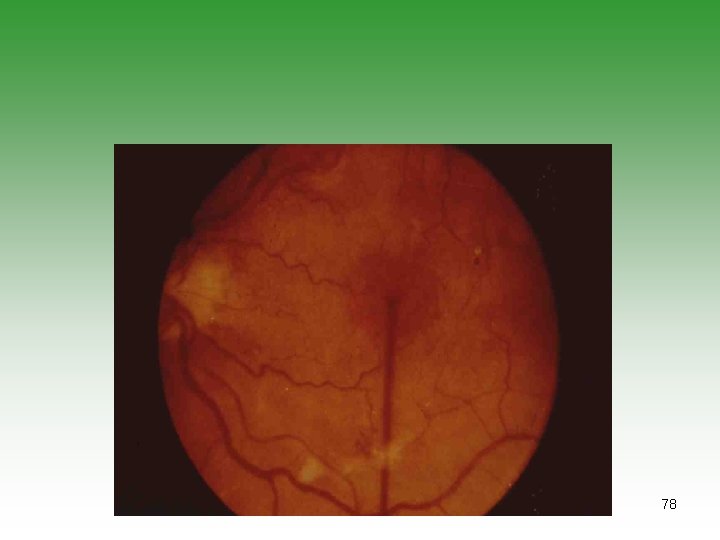

NEUROPSYCHIATRIC MANIFESTATIONS Ø Non-Focal Cerebral Dysfunction (35 -60%) organic brain syndrome. Psychosis. Neurosis. Ø Movement Disorders (10 -35%) Ø Seizures (15 -35%) Ø Focal Deficits (10 -35%) Ø Peripheral Neuropathies (10 -25%) Ø Others: e. g. headach , aseptic meningitis, mysthenia gravis 77

78